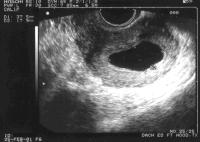

Tanısı ultrasonda embryo ve kalp atımları görülmesi gereken haftalarda kesenin boş olarak izlenmesi ile konur. Erken gebelikte konulan bir tanı olduğu için bazı özel durumlara dikkat etmek gerekir. Özellikle adet kanamaları düzensiz olan kişilerde yumurtlama beklenen tarihten daha sonra gerçekleşmiş olabileceğinden bu durum özellikle dikkate alınmalıdır.

Boş gebelik ile çok erken dönemdeki normal bir gebeliği ayırdetmenin en önemli yolu kese içinde yolk kesesi adı verilen yapının izlenmesidir. Yolk kesesi varlığı gebeliğin boş gebelik olmadığının en önemli belirtisidir. Öte yandan kesenin ultrasondaki görüntüsü de bu iki durumun ayrımında yol gösterici olabilir. Teorik olarak son adet tarihinden yaklaşık 5 hafta geçen durumlarda transvajinal ultrasonografi ile fetus görülebilmelidir. Bunun gerçekleşmediği durumlarda ise boş gebelik tanısı koymak için aceleci davranmak çok yanlış bir yaklaşım olacaktır. Bu gibi bir durum varlığında en azından bir hafta beklenerek durumun gidişatı hakkında yeterli bilgi edinilmelidir.